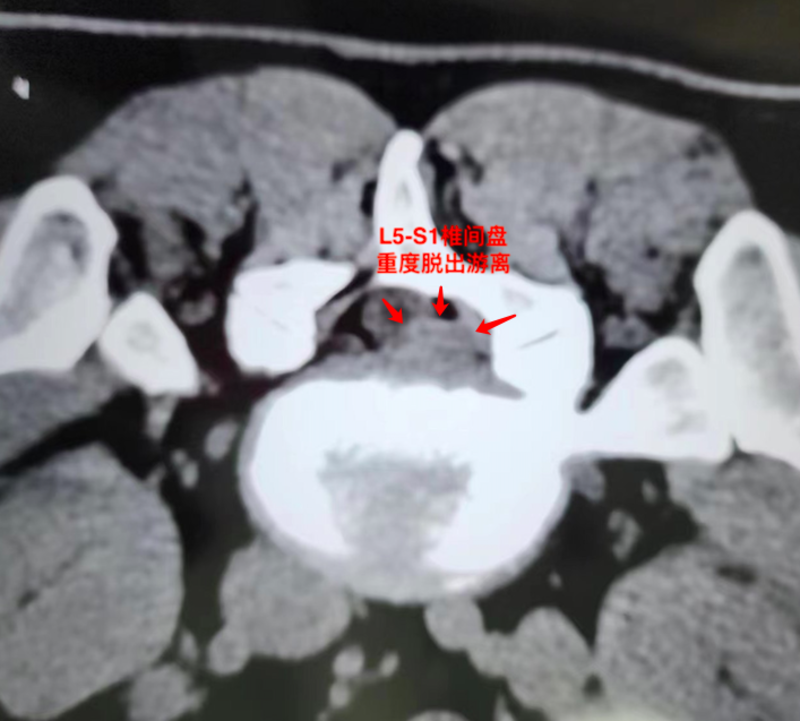

2, 2023.12.23腰椎CT;L5.S1右后脱出游离。L3.4,L4.5椎间盘退变,膨出(见图1)

2023.12.23腰椎CT;L5.S1右后重度脱出游离。

根据该患者严重的病情和巨大椎间盘脱出游离,如果仅仅采取椎管内消炎治疗(童氏精准无创介入治疗,)保守估计康复需要3个月(见图2)通过CT引导把PRP(富血小板血浆)直接注射到无血供组织的椎间盘内,给退变椎间盘撕裂口提供生长因子,创造修复条件,让退变椎间盘纤维环内中外三层组织结构均可以得到修复,这样不仅大大缩短了撕裂口修复的时间,同时也增强了椎间盘纤维环的坚固度。